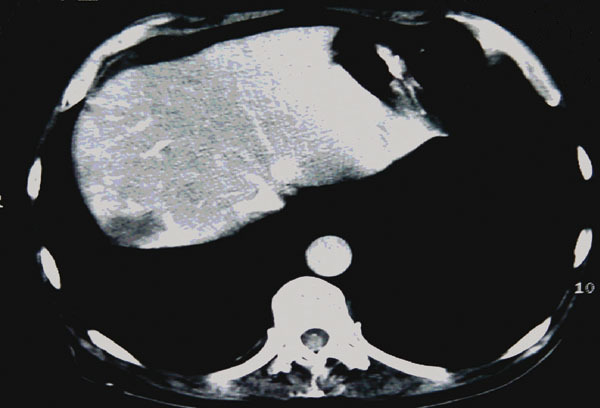

La Revue du Praticien - Jacques Belghiti Image unique hypodense avec un halo hypervasculaire périphérique.